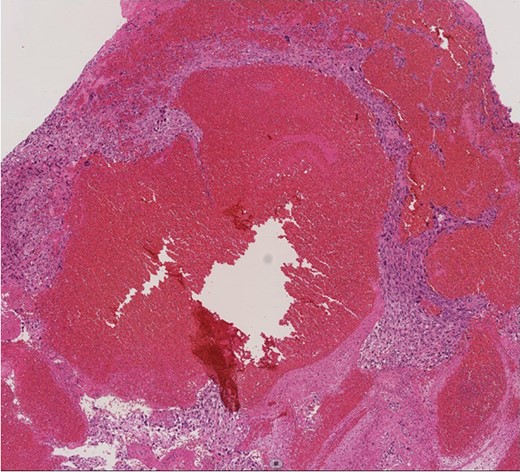

A 60-year-old man presenting with acute onset dyspnea and chest pain was referred to our institution. He had no past medical history. Physical examination was essentially normal except for weak respiratory sounds on the right side. Oxygen saturation was 88%. D-dimer was 1.43 mg/l. The electrocardiogram showed no ST changes. Chest radiography showed an abnormal shadow in the hilum of the right lung. Color Doppler ultrasound showed no deep vein thrombosis. Both the Wells Score and the Revised Geneva Score were 0. Transthoracic echocardiography showed normal left ventricular function (ejection fraction 62%), and no findings of pulmonary hypertension. Contrast-enhanced computed tomography (CT) showed a contrast defect lesion in the right and main pulmonary arteries, as well as a right pleural effusion (Fig. 1). He was initially diagnosed with PE according to the imaging findings and clinical presentation. Anticoagulant therapy (intravenous heparin infusion) was then started. Follow-up CT showed a larger defect lesion in the pulmonary artery, and the decision was then made to proceed with urgent pulmonary embolectomy because it was refractory to anticoagulant therapy. Cardiopulmonary bypass was established with aortic and bicaval cannulation. Deep hypothermic circulatory arrest was used every 10 minutes to obtain a bloodless field during pulmonary embolectomy. The right pulmonary artery was incised, and it was filled with a red, solid mass (Fig. 2). The mass was resected, and the pathological diagnosis during surgery was PAS. Because of the urgent situation, only endarterectomy, not pneumonectomy for radical resection of the tumor, was performed. On postoperative Day 7, CT showed residual lesions in the right pulmonary artery. The pathology report showed high-grade undifferentiated PAS (Fig. 3). The patient refused radical tumor resection by pneumonectomy, as well as postoperative radiation and chemotherapy. He died 5 months after the surgery.

Histopathological image (×100). Histologic analysis of the specimen shows high-grade undifferentiated sarcoma due to polymorphism with mitoses and a polychromatic inner lining. Necrotic tissue and thrombi are also present in the tumor, with invasion into the fibrous intima of the pulmonary artery.